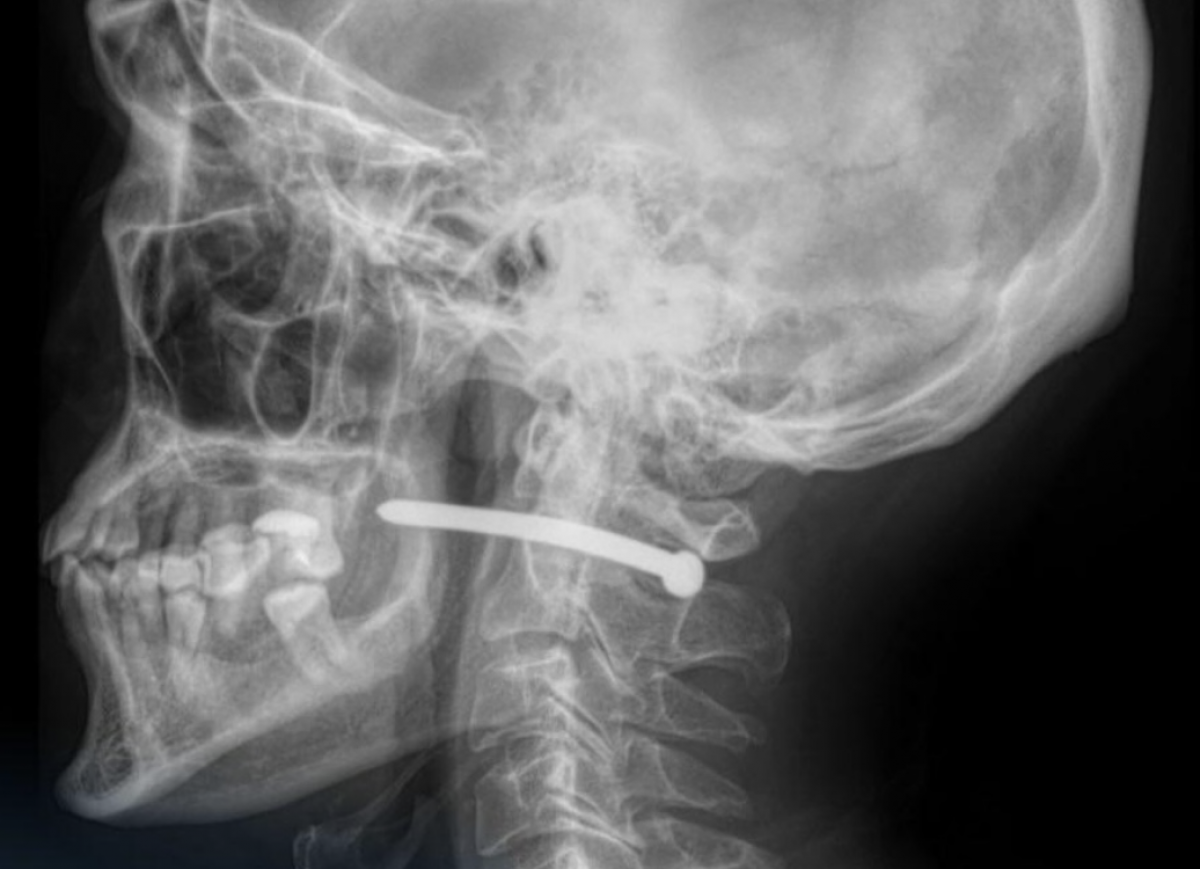

Во время ремонта 51-летний житель Петропавловска получил опасную травму – гвоздь из пневматического пистолета пробил кожу за ухом и прошел всего в нескольких миллиметрах от позвоночника, передает Liter.kz со ссылкой на Petropavlovsk.news.

Инцидент произошел, когда мужчина по неосторожности ранил себя инструментом. С ранением в заушной области он обратился в Многопрофильную городскую больницу скорой медицинской помощи. После рентген-исследования врачи установили, что гвоздь прошел рядом с шейным отделом позвоночника. По словам медиков, мужчине повезло – жизненно важные структуры не были задеты.

"Челюстно-лицевыми хирургами проведено удаление инородного тела, ревизия и обработка раны. После наложения швов и стерильной повязки пациент с рекомендациями отпущен домой", – сообщили в медучреждении.